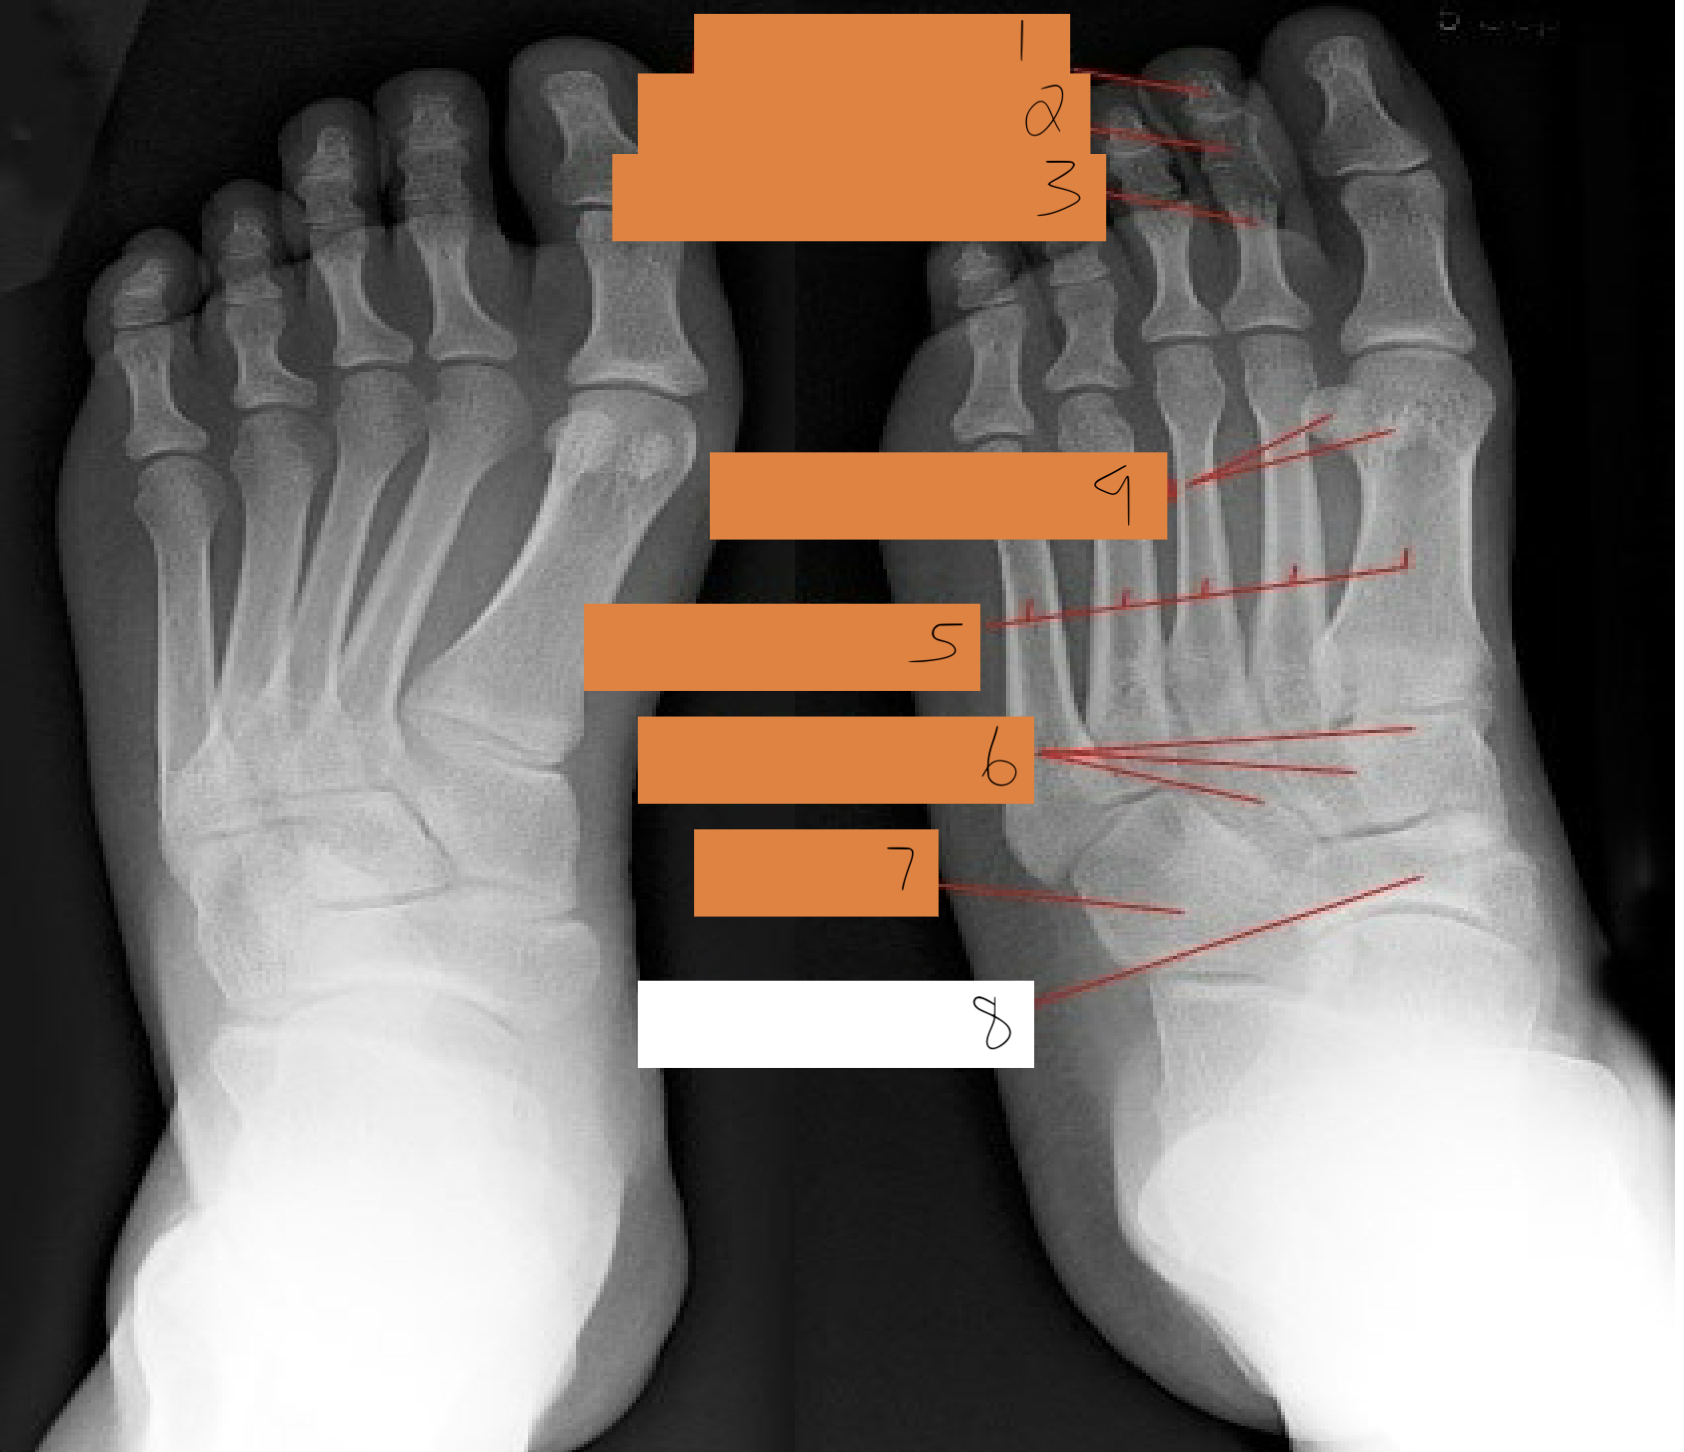

1

distal phalanx

2

middle phalanx

3

proximal. phalanx

4

sesamoid bones

5

metatarsals

6

cuneiforms

7

cuboid

8

navicular